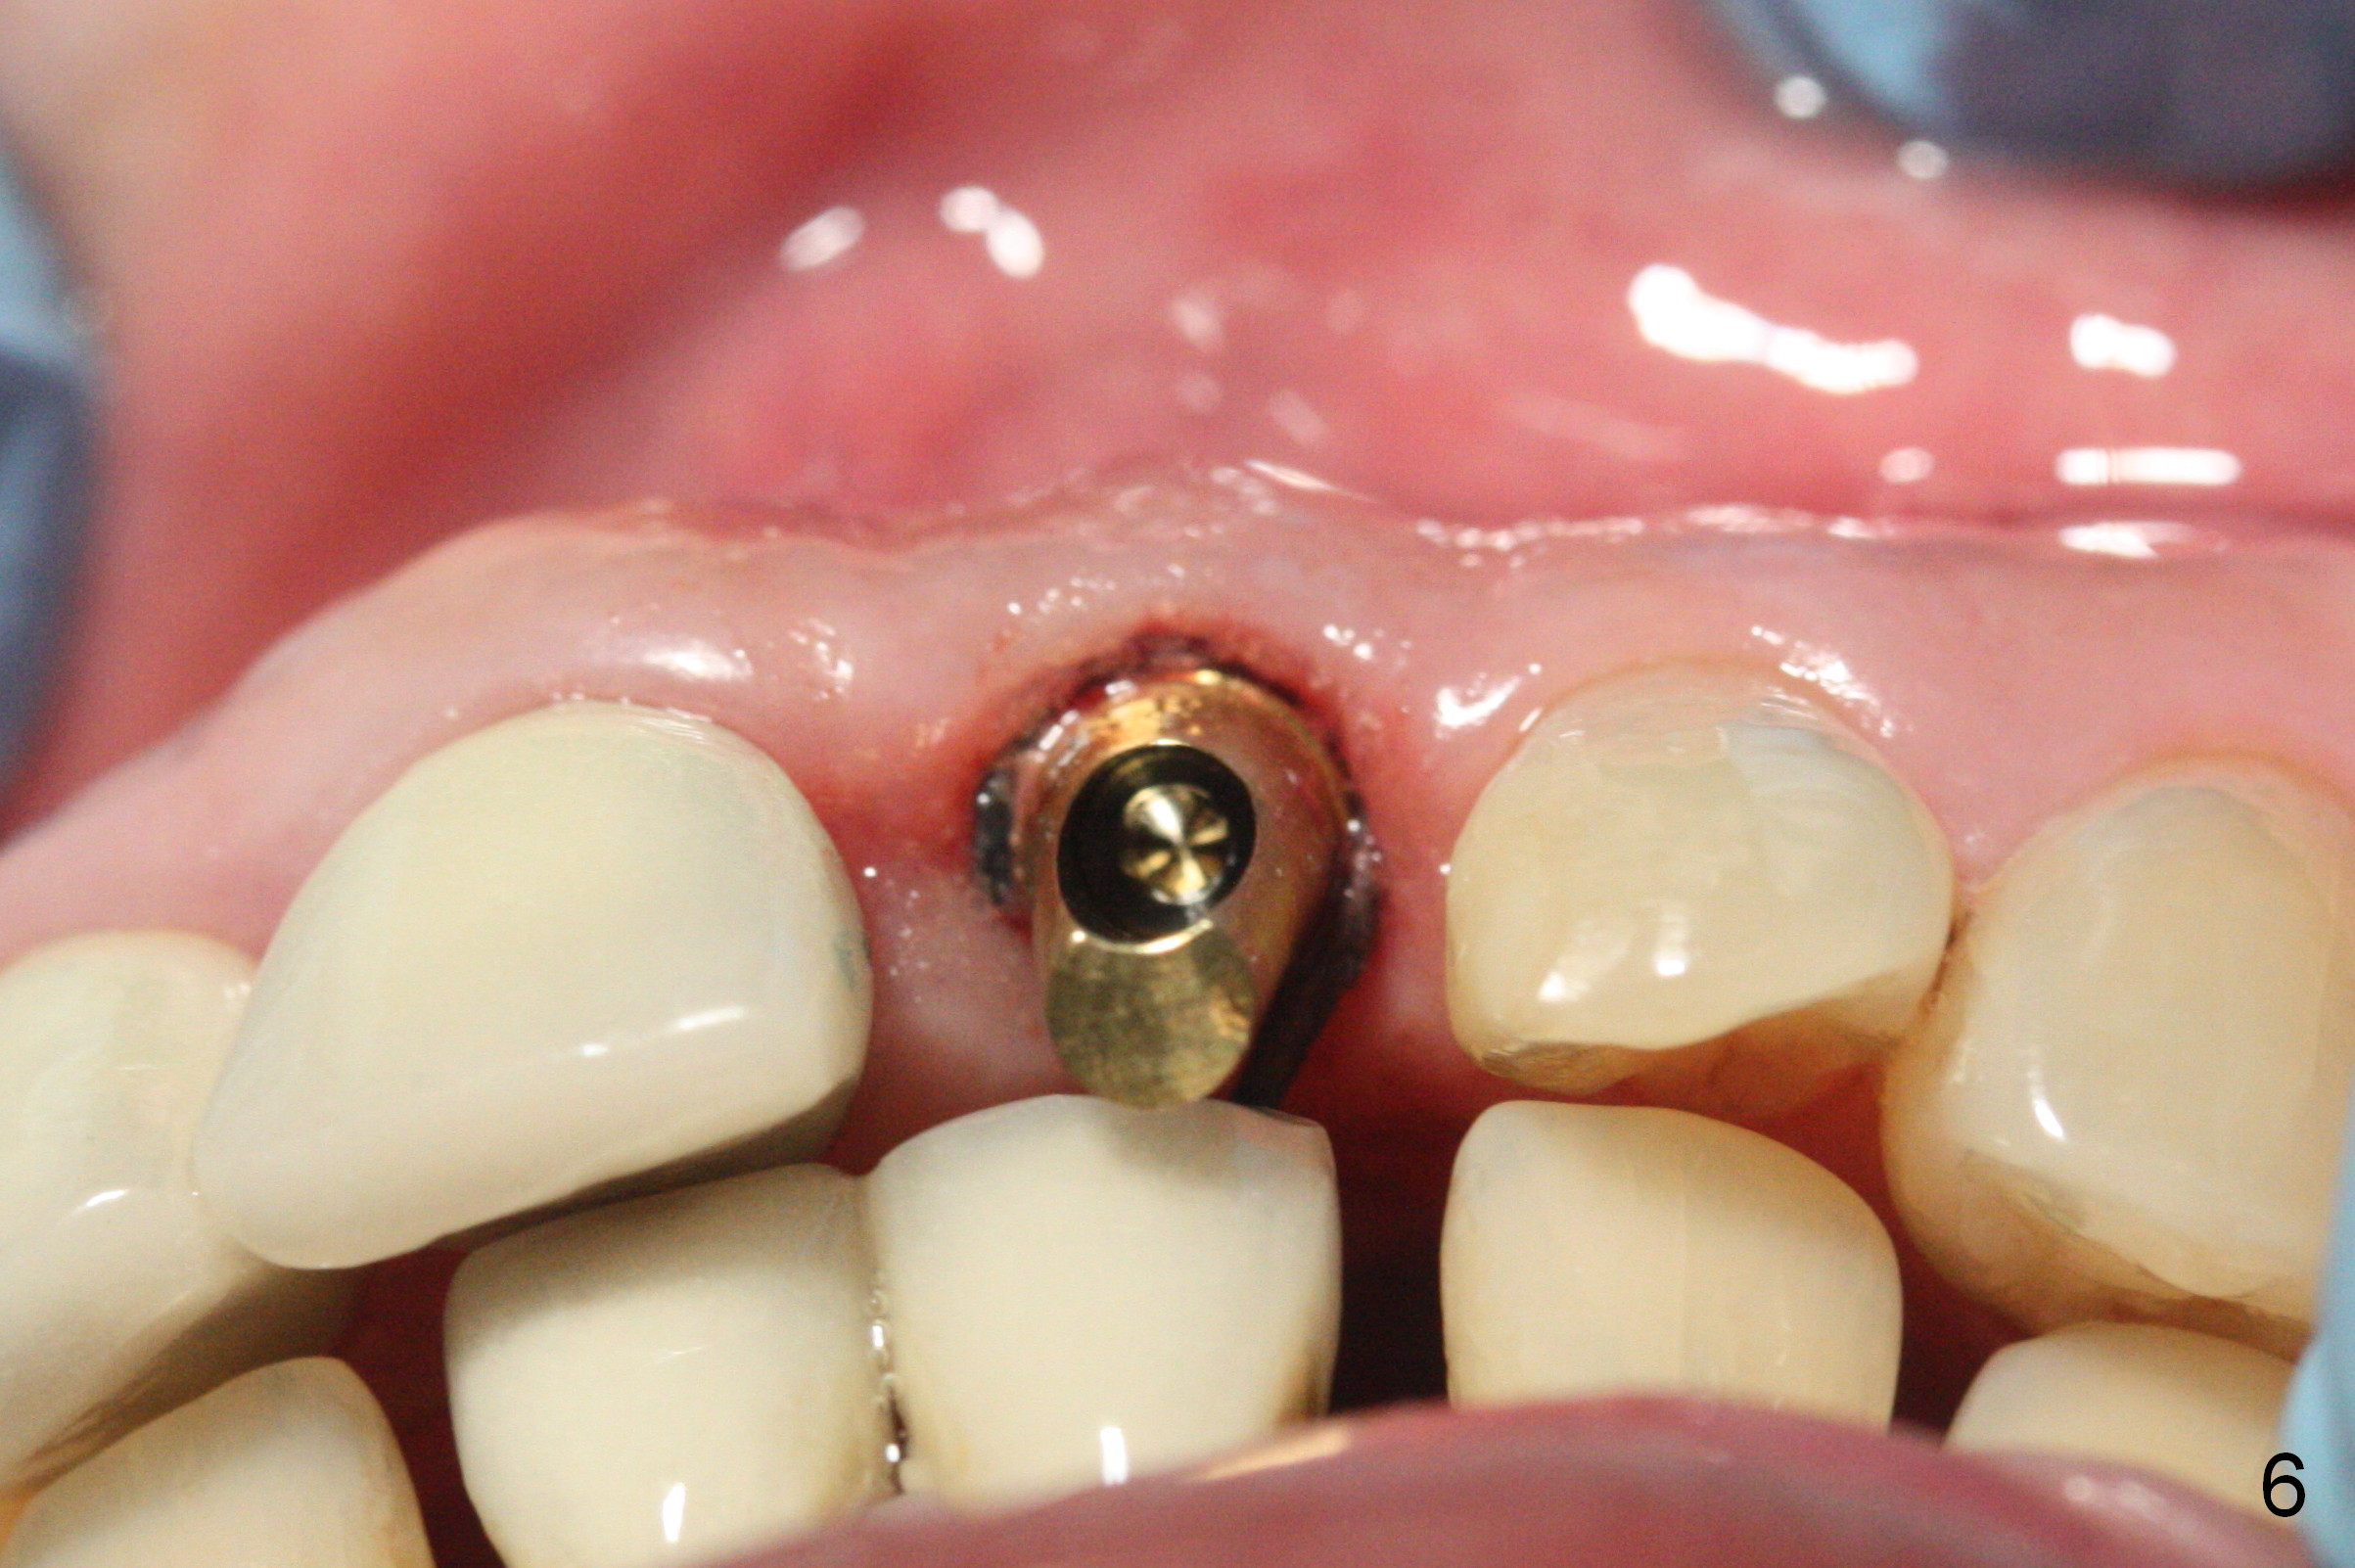

Gold-Coated Angled Abutment

When a permanent crown (Fig.1 C) is seated 5 months postop, it looks too long and bulky (as well as metal show through cervically), which is in turn due to buccal placement of the crown (Fig.2) and abutment (Fig.3). By mistake, abutment is changed from 4.5x15°, 3 mm cuff to 4.5x15°, 2 mm cuff (Fig.4-6); the profile appears to improve. After prep (buccoincisal (Fig.4 ^) and linguoincisal), impression is taken. The gold coating in the buccocervical area is untouched so that there should be no or minimal metal show through. Please make a new crown as cosmetic as possible (not too bulky, especially buccocervical). If you feel that the result will be the same as before, return the case. The angled abutment may be changed 25°. In fact the new crown looks better.